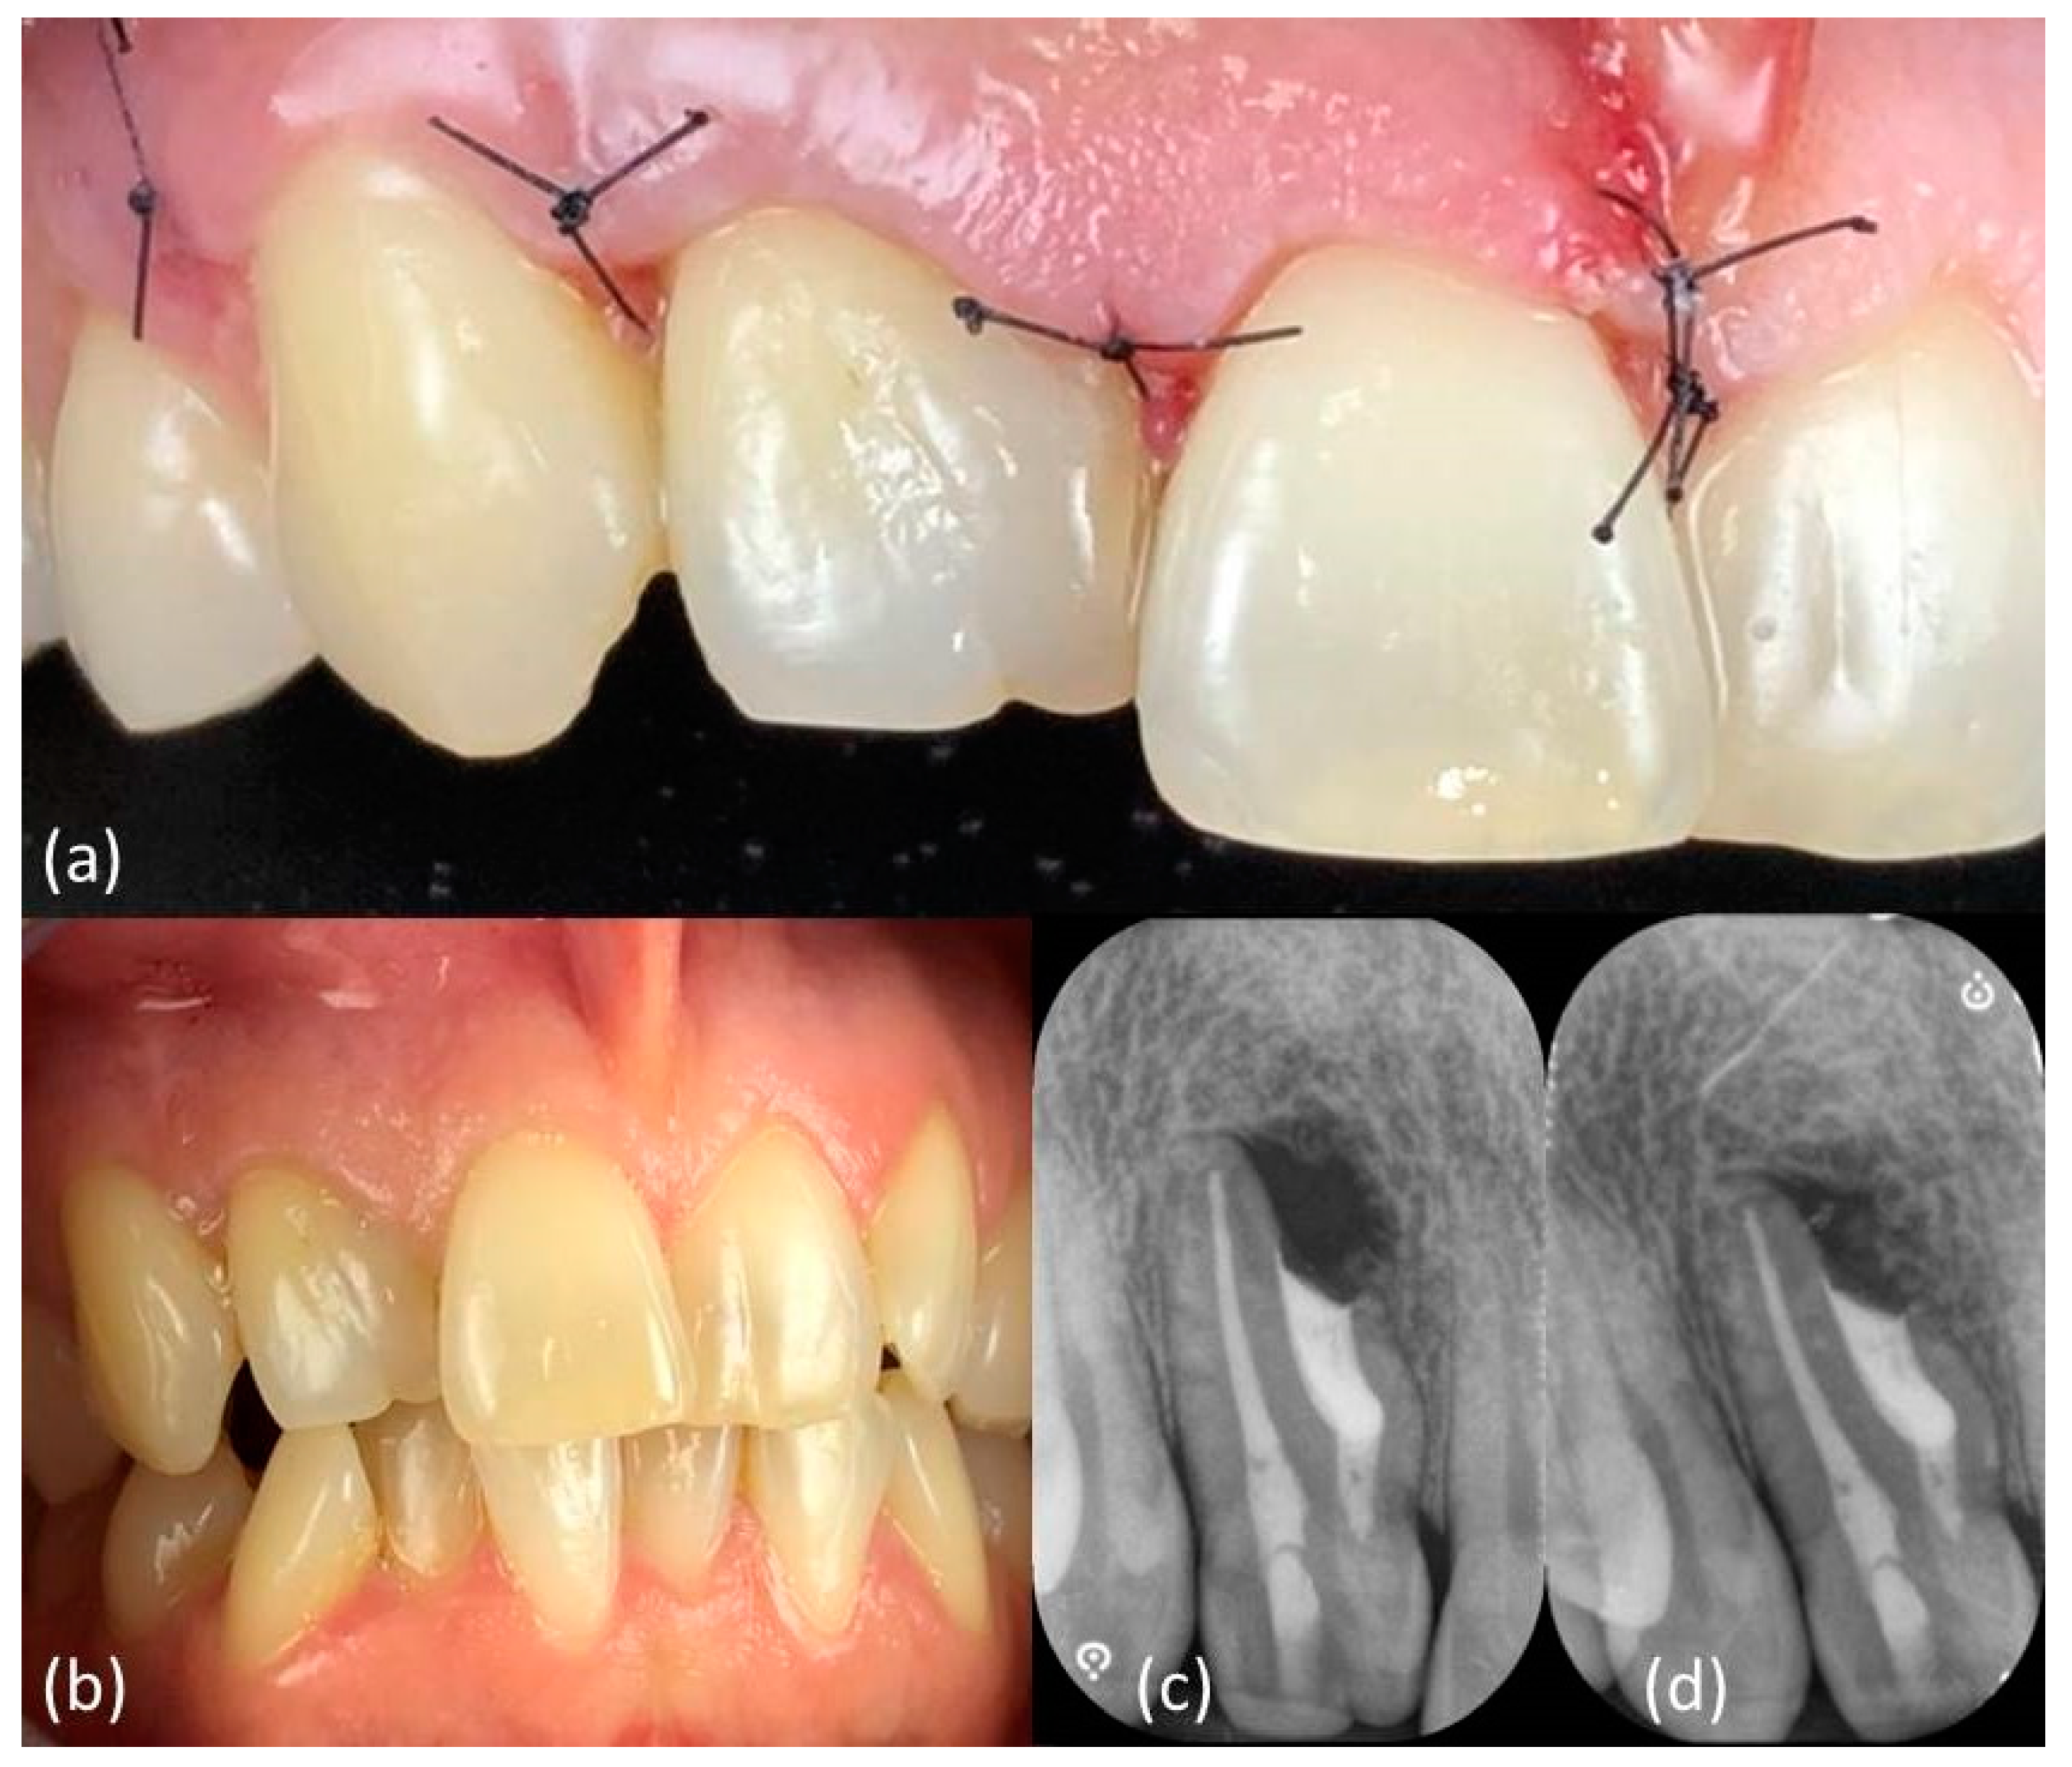

An extraoral examination did not reveal abnormalities. An intraoral examination showed an aberrant coronal anatomy of element 12: the crown was wider mesially, with a slight irregularity of the incisal edge, hence a dens invaginatus was suspected (Figure 1a); no caries or restoration were detected.

Figure 1.

(a) Intraoral examination showed a wide crown of element 1.2, typical anatomy of a dens invaginatus. (b) Periapical X-ray showed a mesial invagination separated from the main distal canal (dens invaginatus type3a), with an apical radiolucent area. (c) CBCT confirmed these findings.

Imaging examination and diagnosis: A long cone periapical (LCPA) X-ray (Figure 1b) was taken (X-minD™ Unity, ACTEON® IMAGING, Merignac, France). Dens invaginatus type3a anatomy [35] was confirmed and chronic apical periodontitis was diagnosed, with a radiolucent area on the mesial aspect of the root, laterally to the main canal, where the invagination was communicating with the periodontal ligament through a pseudo-foramen; a large periapical radiolucency surrounded the periapex.

A small-FOV CBCT (Orthophos XG 3D, Dentsply Sirona, Charlotte, VA, USA) (Figure 1c–Movie 1) was taken as a supporting examination. The axial slices confirmed that the main root canal, developing from a small distal chamber, was separated from the invagination at all levels; furthermore, it showed that the invagination was limited to the root, not involving the clinical crown of the tooth, the periapical lesion was present both at the main and the pseudo-foramina and that it had perforated both the buccal and the palatal cortical plate.

One week later, no discomfort has been reported and primary tissue healing had been achieved, allowing sutures removal (Figure 5a). Clinical (Figure 5b) and radiographic follow-up (Figure 5c,d) showed a positive outcome, with soft tissue and bone healing progression.

Figure 5.

Tissue healing after (a) one week and (b) six months and (c) six-months and (d) twelve-months radiographic follow-up.